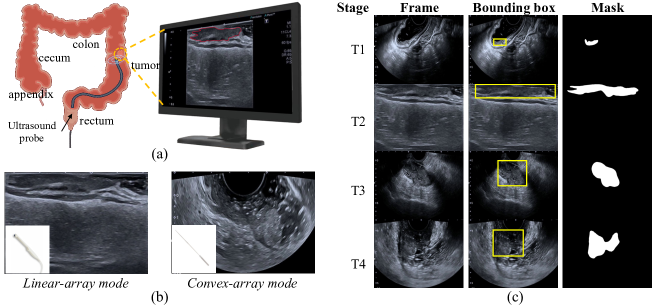

Colorectal cancer (CRC) has become the second leading cause of cancer death worldwide [4]. Accurate early detection of CRC is crucial for making therapeutic decisions and improving the survival rate. Currently, Endorectal ultrasound (ERUS) is adopted as a routine imaging modality for diagnosing and staging colorectal cancer [8]. As shown in Fig. 1(a), ERUS provides in-depth assessments of tumor infiltration, precisely depicting the cancer’s location, size, and its relationship with surrounding tissues [15]. However, the sonographers’s level of experience or fatigue during long duty hours contributes to a non-negligible rate of missed detections in clinical diagnosis. Thus, it is important to develop an automatic system for computer-aided diagnosis of CRC from ERUS videos.

Refer to caption

Figure 1: (a) Schematic diagram of ERUS operation. (b) Different scanning modes of ultrasound. (c) Examples of our ultrasound video dataset with corresponding labels.

Previous works have proposed well-annotated ultrasound datasets and corresponding methods, covering various organs such as the breast, pancreas, and thyroid [7, 10, 13]. Li et al. [10] pioneer the application of deep neural networks in the diagnosis of pancreatic diseases using Endoscopic Ultrasound (EUS). Wang et al. introduce a 3D feature pyramid network to conduct inter-frame collaboration. Li et al. [11] propose a memory bank and dynamically update the memory to establish long-term temporal correlation. Building upon this, Lin et al. [13] extend the approach by incorporating Fourier transforms to aggregate multiple features from the frequency domain. Despite significant advancements achieved by those methods, accurate colorectal cancer segmentation in ERUS remains challenging due to (1) the scarcity of large-scale endorectal ultrasound datasets to train well-converged segmentation models, (2) the intrinsic scanning mode discrepancy obtained from different ultrasound sensors, as illustrated in Fig. 1(b), and (3) the motion blur resulted from a rapidly moving ultrasound probe.

Endorectal Ultrasound Dataset To facilitate advancements in colorectal cancer segmentation and the staging of tumor infiltration depth, we collected and annotated the first endorectal ultrasound dataset, named ERUS-10K, consisting of 77 endorectal ultrasound videos with a total of 10,000 annotated frames. All patients underwent endorectal ultrasound examinations at the Affiliated Hospital of North Sichuan Medical College using CANNO-type color Doppler ultrasound diagnostic apparatus. Among 77 videos, 19 videos were recorded using the linear-array scanning mode by 11CL4 rectal cavity probe, while the remaining utilized the convex-array scanning mode by the vaginal probe. Fig. 1(b) illustrates the differences between these two scanning modes. Manual annotations of colorectal cancers were performed by experienced sonographers. The provided annotations include colorectal lesion masks and bounding boxes, comprehensively covering clinical scenarios ranging from colorectal lesion detection to segmentation. Furthermore, 57 videos implemented pathological examinations via percutaneous biopsy to determine the tumor infiltration depth (i.e. stage T1, T2, T3, T4), laying the foundation for automated and precise colorectal cancer staging. Fig. 1(c) displays sample images along with their corresponding labels. The entire dataset is divided into training, validation, and test sets in a ratio of 7:1:2, enabling a comprehensive benchmark evaluation of our proposed methods. Fig. 4 shows the detailed statistics of the dataset.